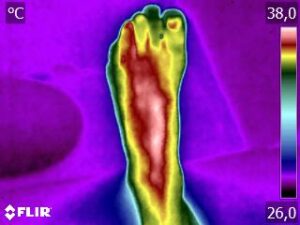

Como no caso da sequência de termogramas abaixo de uma paciente do sexo feminino, 51 anos e sem comorbidades e que sofreu um trauma de pé esquerdo durante a prática esportiva. Fez exame de Raio-X e não foi detectado fraturas, mas ainda apresentava muita dor. No 4º dia de pós trauma realizou uma Análise Termofuncional e foi detectado alterações térmicas condizente com processo inflamatório.

A terapia então foi ajustada para tratar esta lesão, não sobrecarregando a mesma e não apenas tratando a sintomatologia, mas sim até sua completa restauração.

Como no caso apresentado acima, a Termofuncional lhe proporciona não só “enxergar” as alterações térmicas, mas também uma maior segurança na terapia, com isso você poderá ter resultados muito mais eficazes. Além de lhe garantir segurança jurídica para cada procedimento que você realizar na sua reabilitação.